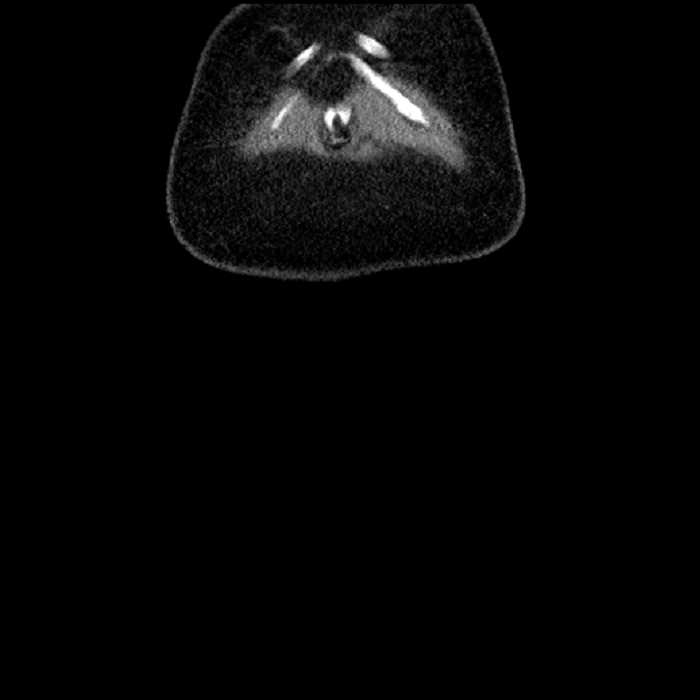

Age: 63

Sex: Male

Indication: Abdominal pain

• Mild mural thickening of a segment of the sigmoid colon with adjacent fat stranding and a 1.5 cm fluid and gas collection along the tip of an inflamed diverticulum

• Loss of the normal fat plane between this collection and adjacent loops of small bowel, which demonstrate mural thickening

Acute sigmoid diverticulitis complicated by a small contained perforation and a large abscess in the right hepatic lobe. Additional small subcapsular abscesses along the anterior margin of the left hepatic lobe.

Additionally, loss of the normal fat plane between the peridiverticular collection and adjacent thickened loops of small bowel raises the potential for an enterocolonic fistula.

Hepatic abscess showing the double target sign with low density internally surrounded by a thin inner enhancing rim (red arrow) and ill-defined outer low density rim (yellow arrow). Blue arrow indicates an internal septation. Red arrows: additional smaller subcapsular abscesses. Red arrow: focal contained perforation associated with diverticulitis.